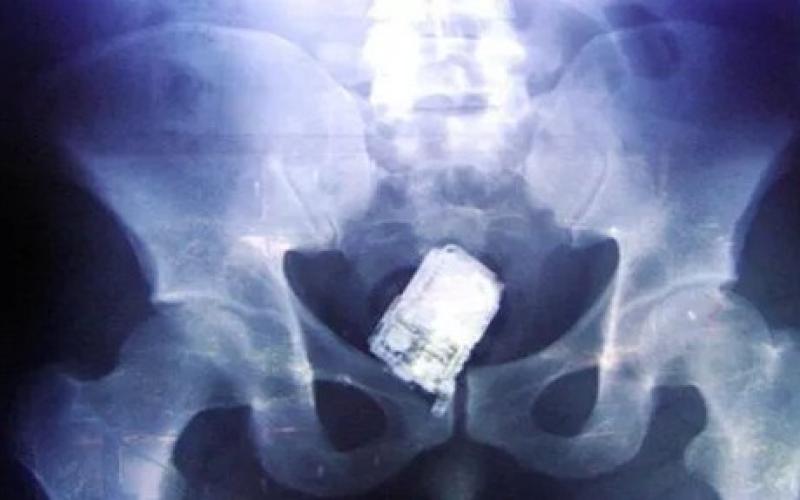

الصحة تكشف حقيقة نسيان هاتف خلوي ببطن مريضة

نفى وزير الصحة الدكتور سعد جابر صحة فيديو وخبر مفبرك يشير الى نسيان احد الاطباء هاتفه في بطن مريضة .

وقال جابر ان الفيديو تم تداوله عام 2015 وتم نفيه أنذاك لعدم صحته. وقال: ان وزارة الصحة نفت الحادثة عام 2015 واوضحت ان المريضة المقصودة كانت قد اجري لها عملية قيصرية بنيسان 2015، في احد المستشفيات العامة وبعد اسبوعين من العملية راجعت المستشفى نتيجة الام كانت تعاني منها .

واشارت الوزارة بتوضيحها انه بفحص وتصوير المريضة تبين ان الالام التي كانت تعاني منها ناتجة عن التهاب جرح العملية وقد تم ادخالها المستشفى على الفور والمباشرة في علاجها وخرجت من المستشفى بعد اتمام العلاج معافاة لا تعاني من اي مضاعفات .

و اكد جابر ان اعادة تداول مثل هذه الاخبار القديمة والغير صحيحة والمفبركة من شانها الاضرار بسمعة القطاع الطبي الاردني بمختلف مكوناته واساءة بالغة تؤثر سلبا على الاقتصاد الوطني والاطباء الاردنيين المشهود لهم بالكفاءة والتميز في عملهم. واهاب بمواقع التواصل الاجتماعي عدم تداول الاخبار غير الصحيحة والتأكد من دقة ما يتداولون قبل النشر .